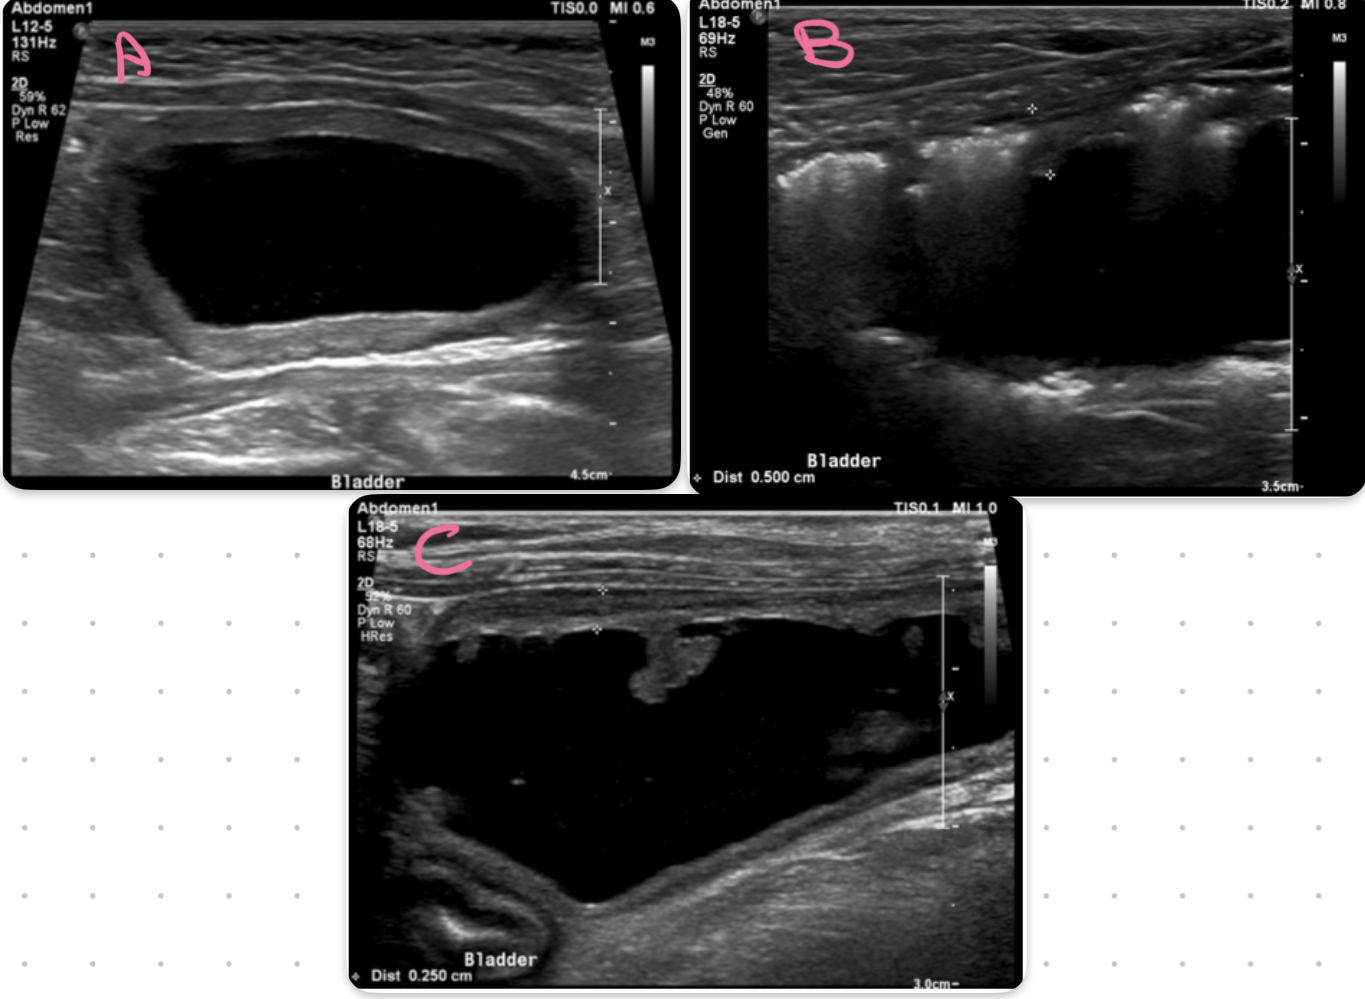

bladder

A = cystitis

B = emphysematous cystitis

C= polypoid cystitis

key ultrasound feature of cystitis

irregular thickened hypoechoic urinary bladder wall

what part of the bladder is most affected by cystitis

cranioventral aspect

neoplasia of the bladder likes to affect what region

trigon and dorsal wall